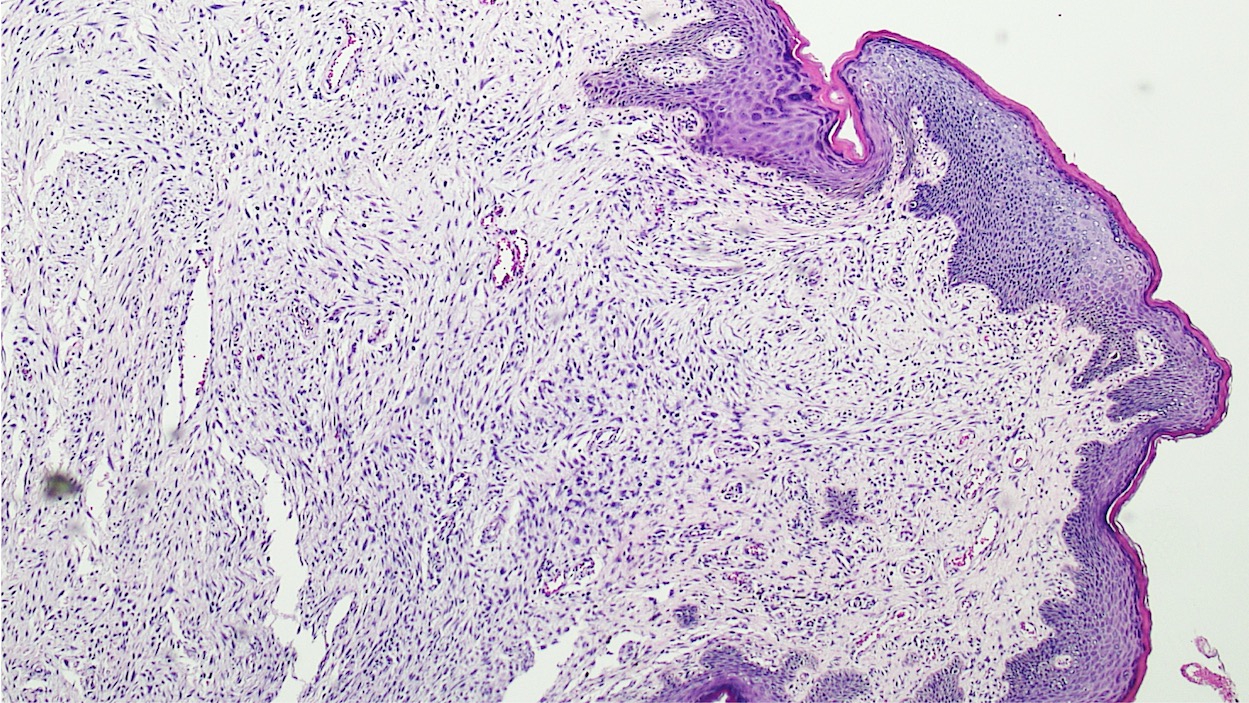

Microscopic (histologic) description

- Polypoid and noncircumscribed, extending to the epithelial / subepithelial interface (J Low Genit Tract Dis 2011;15:69, Am J Surg Pathol 2000;24:231)

- 2 stromal cellularity variants: hypocellular form (spindle cells set within a loose collagenous myxoid-like stroma) or hypercellular variant (exhibits marked nuclear pleomorphism and frequent mitoses, including atypical forms), especially during pregnancy, therefore mimicking leiomyosarcoma or rhabdomyosarcoma (Am J Surg Pathol 2000;24:231)

- Overlying squamous epithelium may display reactive changes but without papillomatous architecture or koilocytosis, which distinguishes it from condyloma acuminatum (caused by human papillomavirus) (Am J Surg Pathol 2005;29:460)

Microscopic (histologic) images